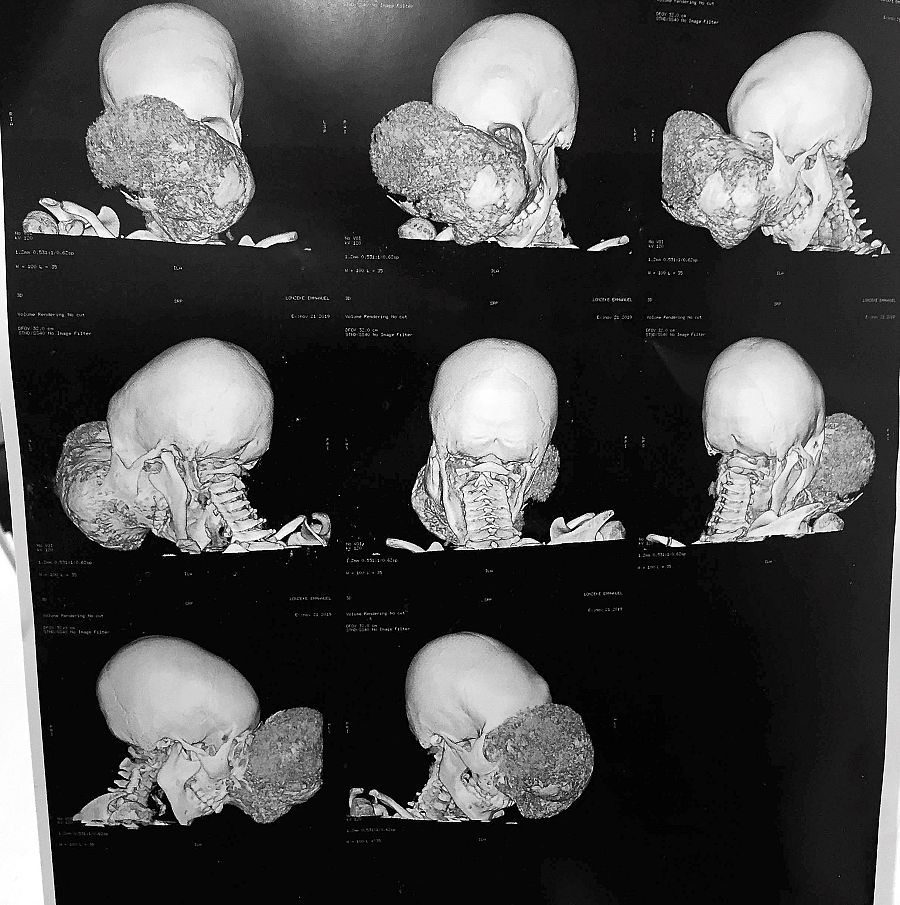

TAC con diferentes imágenes del tumor de Emmanuel antes de la operación.

TAC con diferentes imágenes del tumor de Emmanuel antes de la operación. EFE / FUNDACIÓN PEDRO CAVADAS